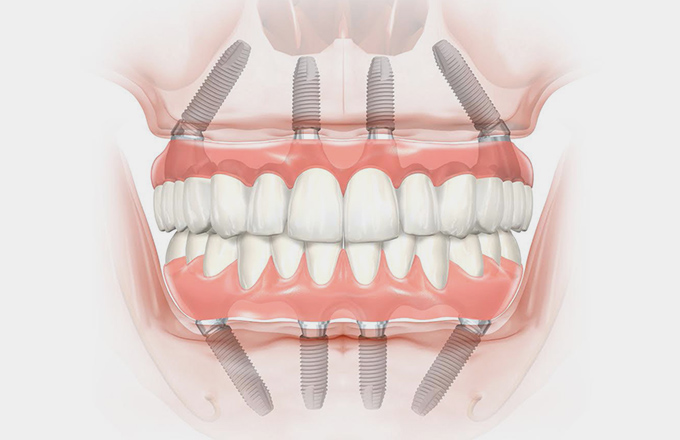

Pokud jde o inovativní stomatologické postupy, „All On Four in Istanbul, Turkey“ vyniká jako prominentní řešení pro jednotlivce, kteří trpí ztrátou zubů nebo významnou degradací zubů. Tato transformační stomatologická procedura mění hru pro ty, kteří chtějí obnovit svůj úsměv efektivně a spolehlivě.

Pokud jde o inovativní stomatologické postupy, „All On Four in Istanbul, Turkey“ vyniká jako prominentní řešení pro jednotlivce, kteří trpí ztrátou zubů nebo významnou degradací zubů. Tato transformační stomatologická procedura mění hru pro ty, kteří chtějí obnovit svůj úsměv efektivně a spolehlivě.

Vzhledem k úpravě zubů se „All On Four in Istanbul, Turkey“ jeví jako přitažlivá a praktická volba, ačkoli cena je společným problémem. Naštěstí Istanbul nabízí špičkové stomatologické ošetření za výrazně nižší ceny než západní země, aniž by byla ohrožena kvalita. Renomované istanbulské zubní kliniky, vybavené nejmodernější technologií a obsluhované vysoce vyškolenými profesionály, zajišťují dokonalost. Cena často zahrnuje komplexní balíčky, díky nimž je „All On Four in Istanbul, Turecko“ nejen cenově dostupné, ale také pohodlné.